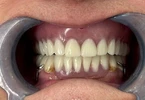

علاج الزرعات السنية